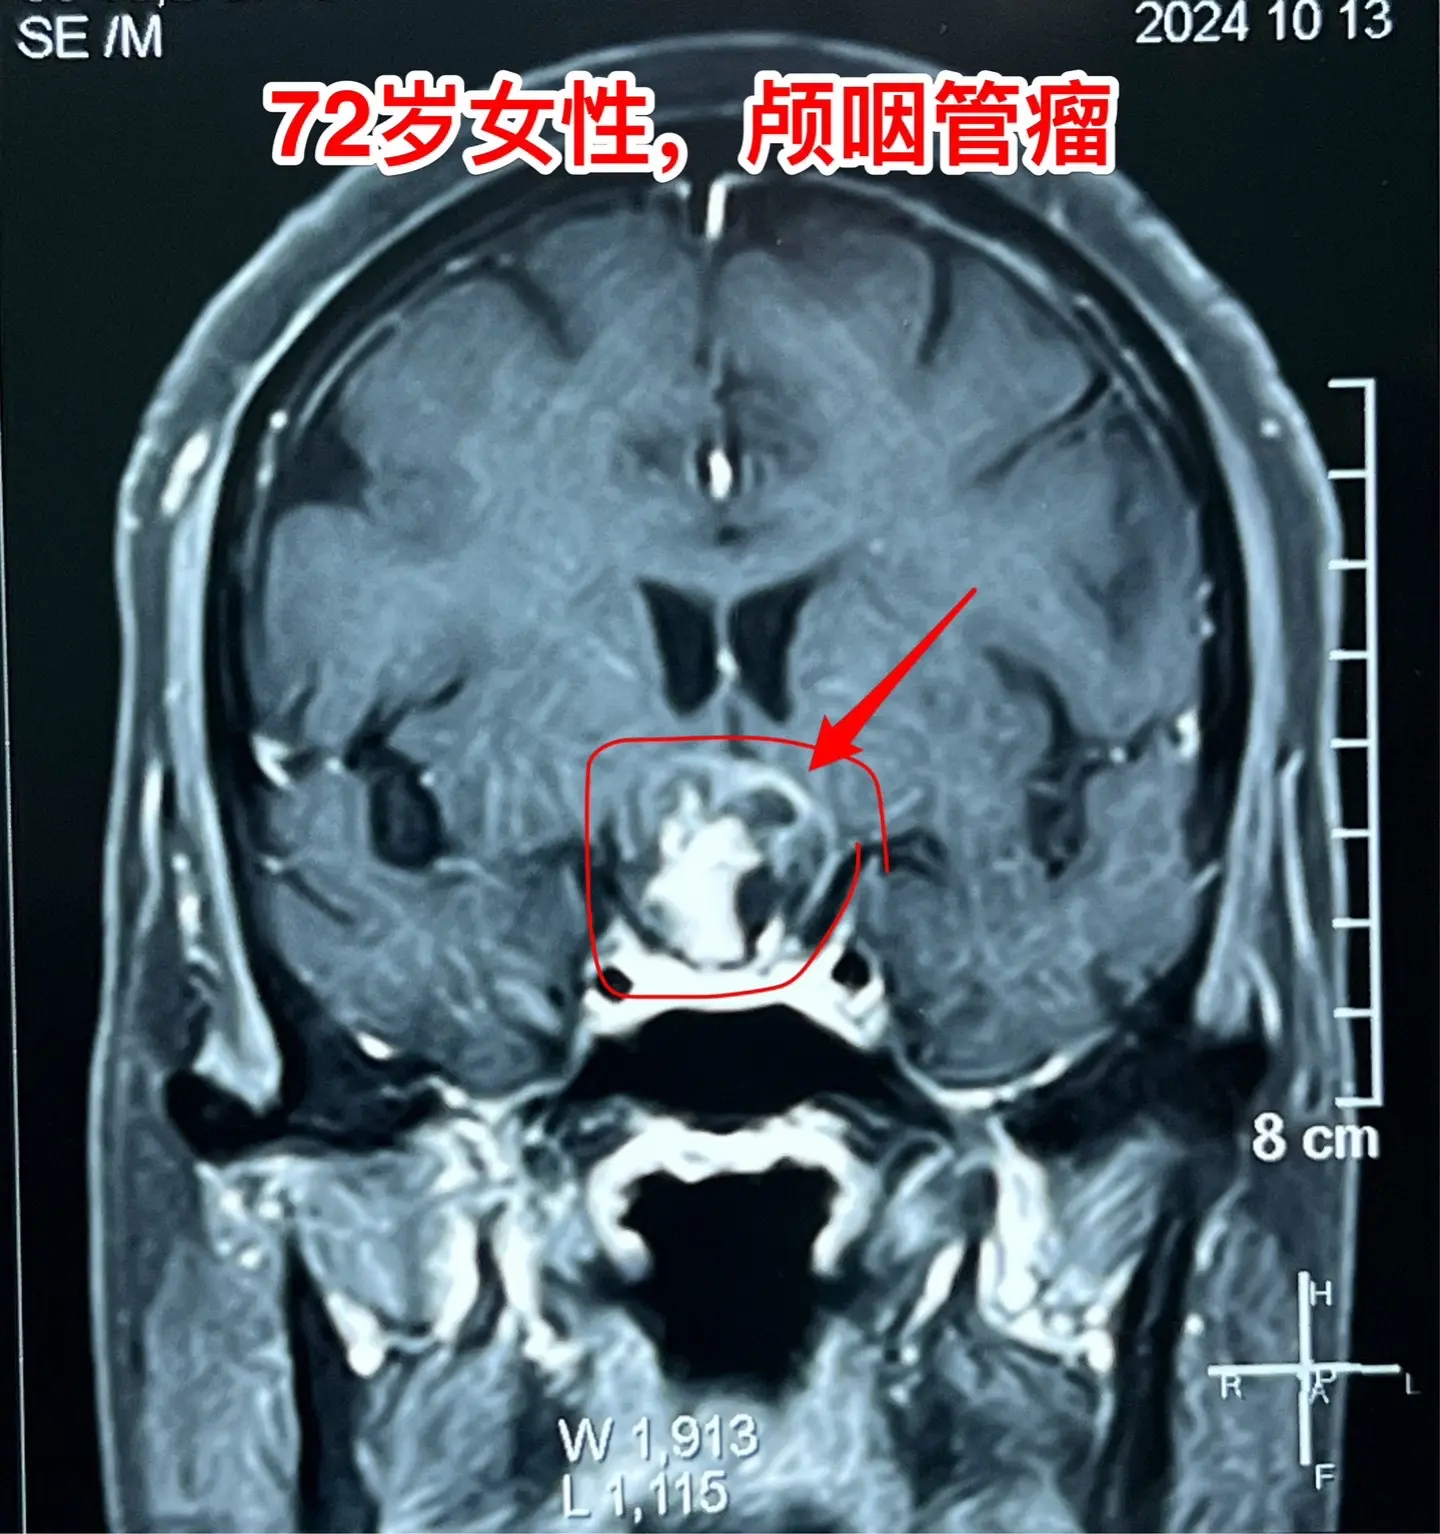

颅咽管瘤不单单是小孩子得的病!很多人认为颅咽管瘤是小孩子得的病,其实各个年龄段的人都可以患颅咽管瘤,我见过的颅咽管瘤病人年龄跨度从不到一岁到八十多岁! 相对而言,小孩子群体中(小于15岁)颅咽管瘤的发生率比较高! 这个72岁的山西晋城市老人在古稀之年患上了颅咽管瘤,病理报告是乳头型颅咽管瘤。10月25日在我科作了手术,11月13日出院。 老人在住院前胃肠功能不好,经常腹胀、消化不良。手术后也是经常感觉腹胀、食欲不振,身体康复过程相对比较缓慢。 老年人一般来说都伴有老年性疾病,比如糖尿病、高血压病、高脂血症、动脉硬化,身体大脏器机能下降,所以老年人患颅咽管瘤,作手术后恢复会比较慢,出意外的风险会增加,尤其是血管方面的并发症会增加,比如深静脉血栓、心肌梗死等。